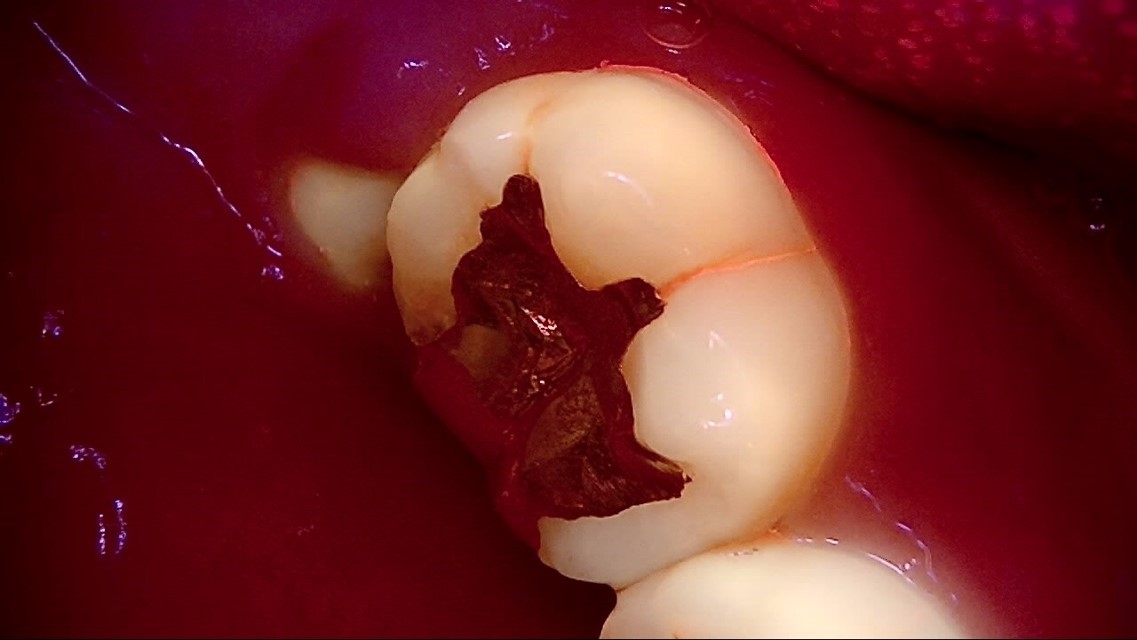

Crack

큐레이캠프로, 큐레이펜씨